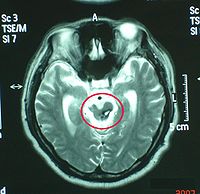

9.MRI 急性颅脑损伤患者通常不作MRI检查。但对病情稳定的弥漫性轴索损伤、大脑半球底部、脑干、局灶性挫裂伤灶和小出血灶、等密度亚急性颅内血肿等,MRI常优于CT扫描。

脑干损伤与继发性脑干损伤的区别在于症状,体征出现的早晚。继发性脑干损伤的症状、体征皆在伤后逐渐产生。颅内压持续监护亦可鉴别:原发性颅内压不高,而继发性则明显升高。同时,CT和MRI也是鉴别诊断的有效手段。在显示脑实质内小出血灶或挫裂伤方面,尤其是对胼胝体和脑干的细微损害,MRI明显优于CT。脑干听觉诱发电位可以较准确地反映脑干损伤的平面及程度。通常在听觉通路病灶以下的各波正常,病灶水平及其上的各波则显示异常或消失,颅内压监护连续测压亦有鉴别原发性或继发性脑干损伤的作用,虽然二者临床表现相同,但原发者颅内压正常,而继发者明显升高。

2.颅脑CT、MRI扫描 原发性脑干损伤表现为脑干肿大,有点片状密度增高区,脚间池桥池四叠体池及第四脑室受压或闭塞。继发性脑疝的脑干损伤除显示继发性病变的征象外,还可见脑干受压扭曲向对侧移位,MRI可显示脑干内小出血灶与挫裂伤,由于不受骨性伪影影响,显示较CT清楚。